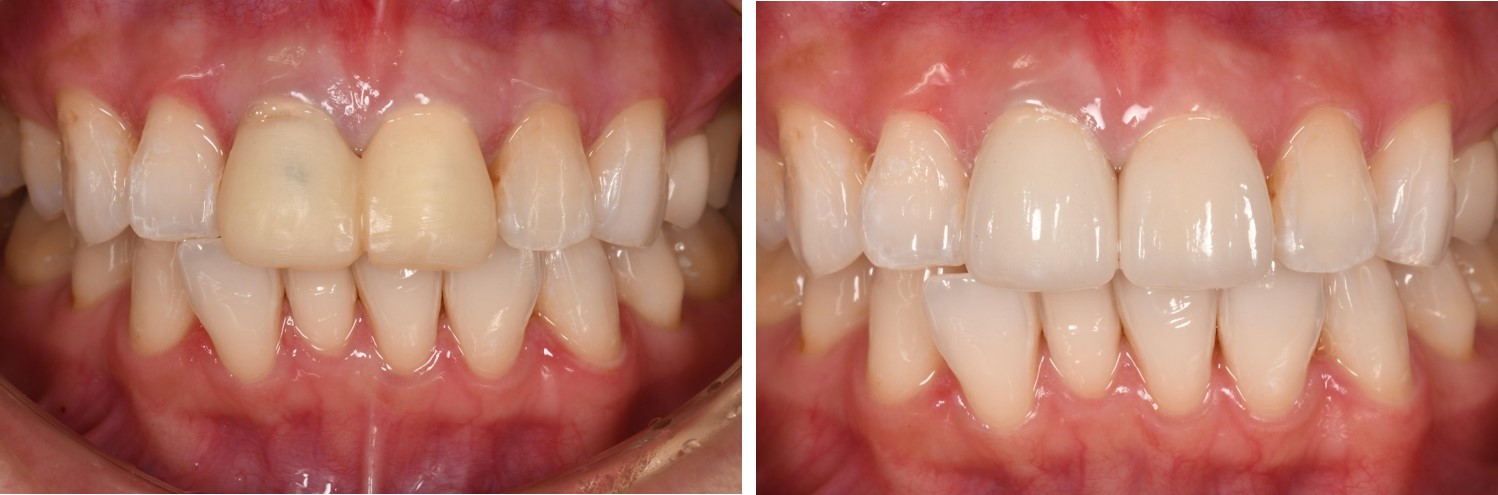

居家美白合併全瓷冠-牙齒變色-#11、21

審美牙科

全瓷冠